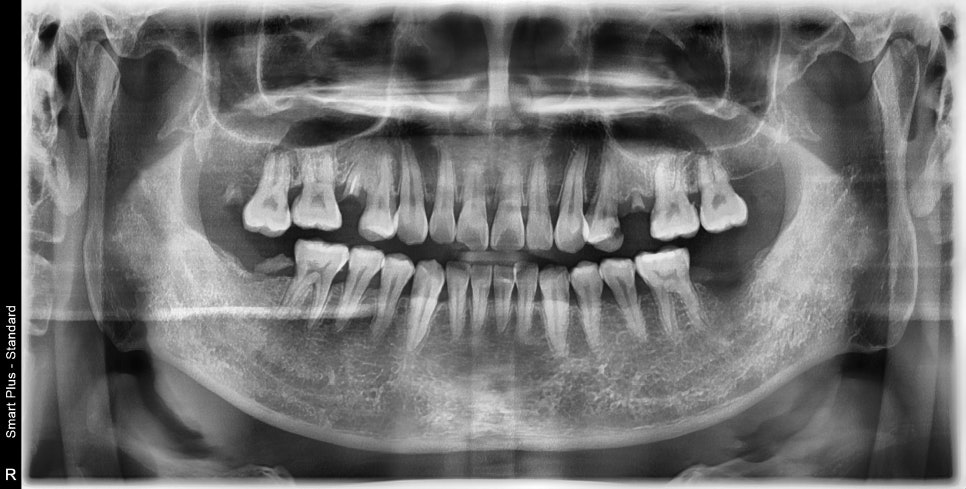

엑스레이, 구강 내 사진을 보게 되면 여러 종류의 치료가 필요한 부위들이 보입니다

충치로 인한 심미적인 부분, 치아 상실 부위, 대합 치아가 없다 보니 아래로 내려온 치아,

깊은 충치로 인한 신경치료가 필요한 치아까지

좌우 다수의 치아에서 치료가 필요했습니다.